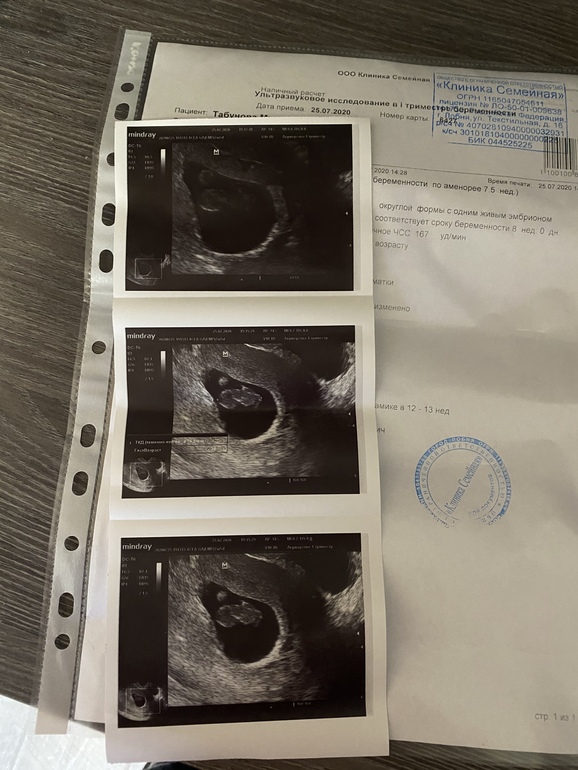

Узи 8 недель)

УЗИ, КТГ, доплерСходили на узи оставлю на память)даже видела как мини человечек шевелит ручками)

Ну не знаю)у меня была ранняя овуляция по узи опережает.31 было повторное узи врач отправил эмбрион был уже 25 мм и шевелился вовсю)